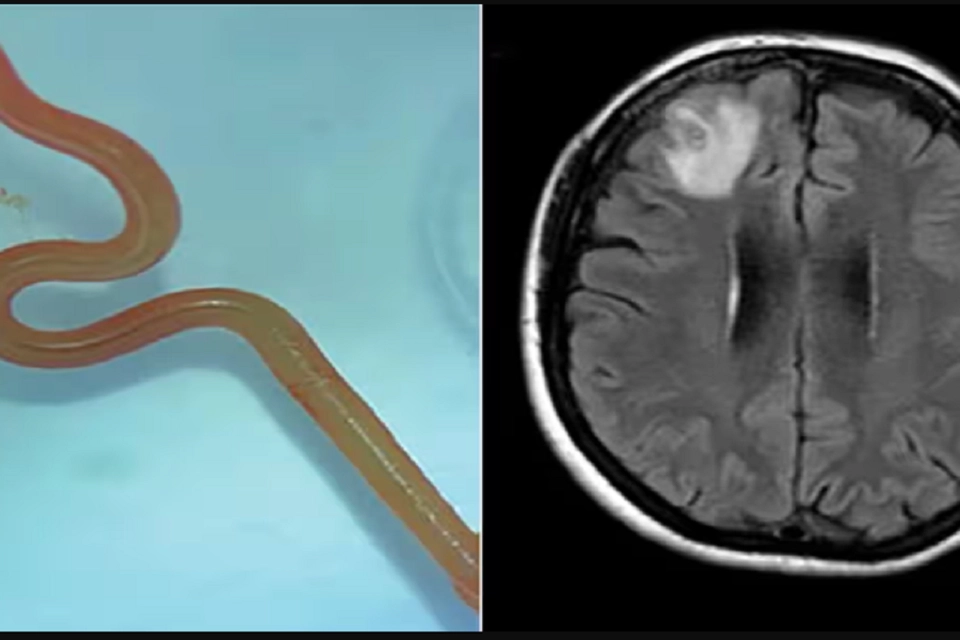

Det, der kom som en overraskelse, var, at under operationen trak neurokirurgen en 8 cm lang parasitisk rundorm ud fra patientens hjerne. Dr. Bandi var i chok og ringede straks til Dr. Senanayake og andre kolleger for at søge rådgivning om, hvordan man skulle håndtere denne utrolige situation.

“Canberra er en mindre by, så vi sendte den stadig levende orm direkte til et laboratorium, hvor en erfaren CSIRO-forsker specialiseret i parasitter kiggede på den og sagde, ‘Dette er Ophidascaris robertsi’,” fortalte Dr. Senanayake.